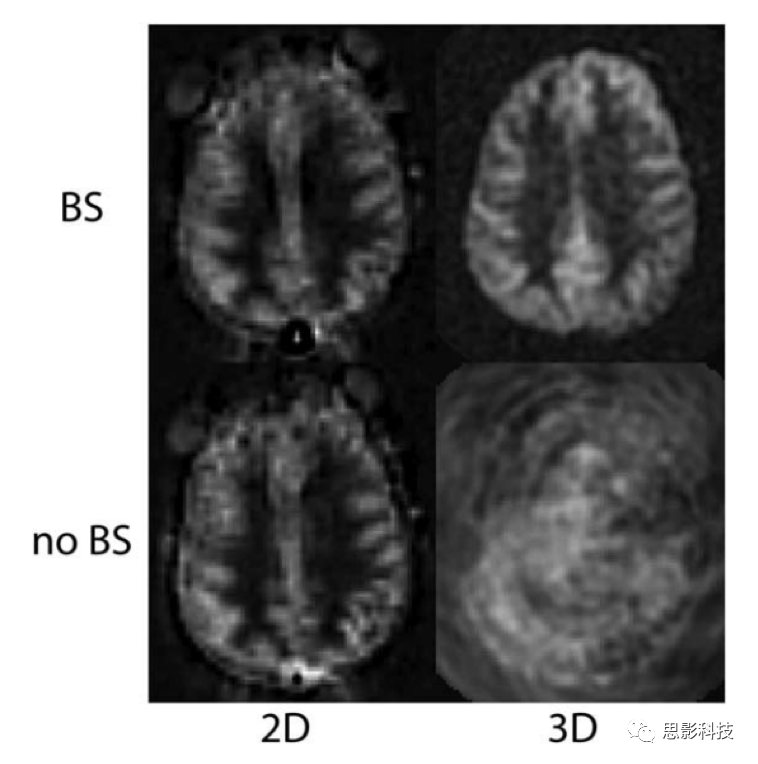

背景抑制方法分析

灰质中每秒有大约百分之一的大脑水分被代谢出去。因此在2秒的测量时间之中每个体素的数值至少会有2%差异。考虑到PLD以及弛豫时间的问题,放松大脑在标注与控制像之间至少会有1%的信号差异。但在采集过程中患者的头部运动成为采集过程中的主要噪声来源。因此,如果能够降低非差值图像的信号强度,而不使ASL差值信号成比例下降,那么ASL测量的整体信噪比可得到显著提高。通过使用空间选择性饱和脉冲和反相脉冲的组合,可以实现未标记的调制信号强度的降低。而这种技术通常称为背景抑制技术。当ASL技术结合背景抑制技术时可显著提高数据的信噪比。尤其是在临床应用这种要求时间特别短,且要求单次扫描即可算出较为准确的脑血流的情况下,背景抑制显得更加重要。

第二个重要的特征在于背景抑制只在某一时刻消除组织的磁化,随后静态组织的磁化随着弛豫恢复到平衡的状态。对于采用每TR一次激发的成像方法,如下面描述的三维分段方法,背景抑制可以是非常有效的,因为磁化零点可以定时与激发脉冲重合。对于每TR需要多次激励的方法,如多分段单脉冲二维(2D)方法,背景抑制对于单个切片是最优的,但对于其他切片的效率逐渐降低。背景抑制效率的差异与ASL成像方法的选择密切相关。

对于ASL的读出模式,三维节段式序列是其首选方案,因为其在每个TR下都施加了一次脉冲激励,对于背景抑制来说这是最佳的设定,因为这种读出方式可有效提高信噪比且相对不受非共振效应的影响。当前来说单次扫描读出应是最优的首选方案,但是这些方法还没有经过严格的测试,不推荐作为一个通用的方案。多层单二维成像读出或者螺旋读出序列,因其普遍适用且不受运动伪影的影响可认为是一个可替代的三维分割序列。但是相对而言,二维的成像方式也存在背景抑制效果差以及扫描时间长等问题。图5为带有2D和3D读取的ASL示例,Vidorreta等人和Nielsen and Hernandez-Garcia更详细地比较了这些方法在ASL中的应用。

作为默认读取方法,推荐使用三维节段方法,如快速自旋回波螺旋式K空间填充叠加方式或3D GRASE方式(一种混合采集方式)。这些方法为ASL脉冲制备的磁化强度的测量提供了接近最佳的信噪比,并且它们对场的不均匀性相对不敏感。它们在纯RARE的读取方法对T2不敏感度,并且与纯EPI或Spiral方法的时间效率之间取得了平衡的处理,从而获得了两者的大多数优点。与2D多层读数相比,这些方法可显著改善背景抑制。背景抑制技术仅在一个时间点时是最佳的,并且由于分段的3D读数在每个TR周期仅需要一次激励,因此可以对激励进行定时以提供高质量的背景抑制。优化背景抑制参数以获得最小的静态组织信号,并且应该计算标记图像和对照图像之间的复杂差异以重建ASL信号,因为接近零的幅度重建图像之间的差异会产生差异。请注意,将背景抑制用于分段3D采集对于ASL至关重要,如图6所示。分段方法需要激发之间的数据一致性,并且在没有背景抑制的情况下,与运动有关的伪影通常将主导ASL信号(如图6所示)。

第二选择是2D单次成像方法,其可有效地应用于ASL。 EPI和螺旋方法已被广泛使用,而单次RARE和平衡SSFP也是可行的,但是不那么常见,并且这种读出方法针对ASL的测试还不够深入。对于ASL,EPI和Spiral的性能,彼此相似,但差异很小。螺旋可以缩短回波时间(TE),以减少T2 / T2 *的权重,但会产生与共振无关的模糊。 EPI具有更长的最小回波时间,但在共振偏移的情况下会表现出失真而非模糊。至于3D成像,建议在特定系统上更好地优化这两种方法中的任何一种。通常,对于单次2D读数,建议使用升序切片顺序。单次成像方法的优点之一是,它们不受运动伪影的影响。对于2D成像,背景抑制技术仅对一个或几个切片而言是最佳的。尽管这通常是一个缺点,但残留的静态组织信号可能会以两种方式使用。首先,可以使用幅度图像重建,它比复杂的重建和线圈组合要简单。第二,残留信号可以在标签与控制相减之前用于图像配准。尽管背景抑制在2D单次成像中的影响远不如3D成像中的剧烈(图6),但可以看到信号波动显著降低,尤其是在患者运动明显的情况下,建议使用背景抑制。有关其他推荐的成像参数,请参见表2。